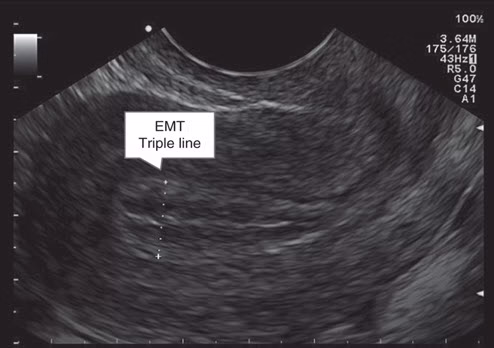

در سونوگرافی، اندومتر در این فاز ظاهری "سه خطی" (Triple-line) یا شبیه به نوارهای راهراه دارد که نشاندهنده یک بافت سالم و پذیرا است (شکل زیر).

در ابتدای فاز قاعدگی یا همان خونریزی ، ضخامت اندومتردر کمترین حد خود قرار داشته و معمولاً بین ۱ تا ۴ میلیمتر (گاهی تا ۵ میلیمتر) گزارش میشود. در سونوگرافی، اندومتر اغلب به صورت یک خط نازک و روشن دیده میشود (شکل زیر) . در این فاز، به دلیل افت سطح هورمونها در پایان سیکل قبلی، لایه ضخیم شده اندومتر ریزش میکند و به صورت خون قاعدگی از بدن دفع میشود.